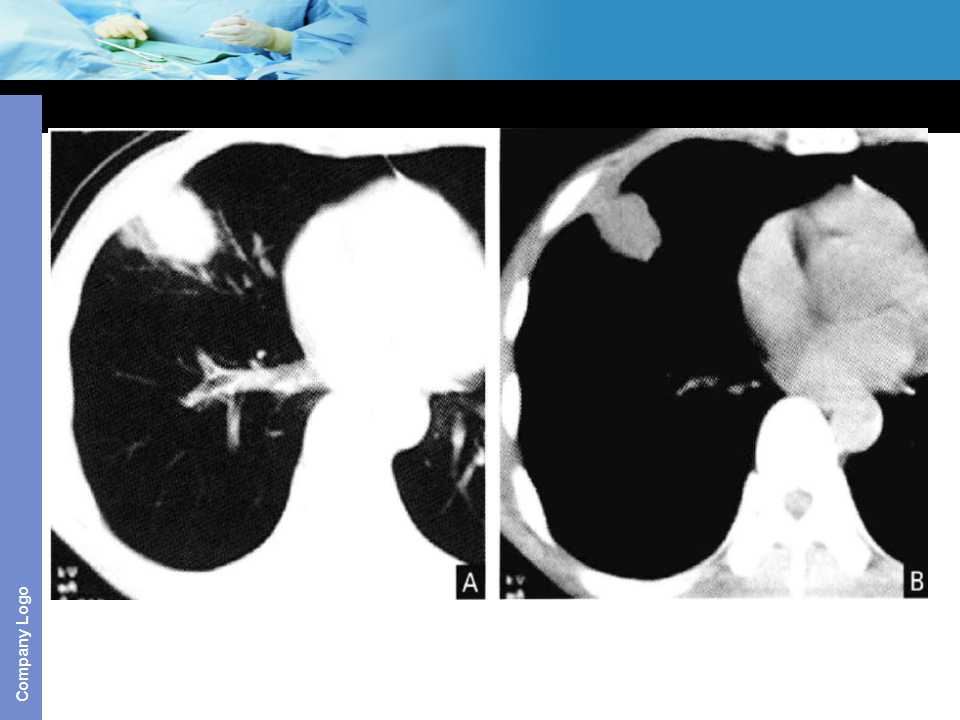

肺癌影像诊断